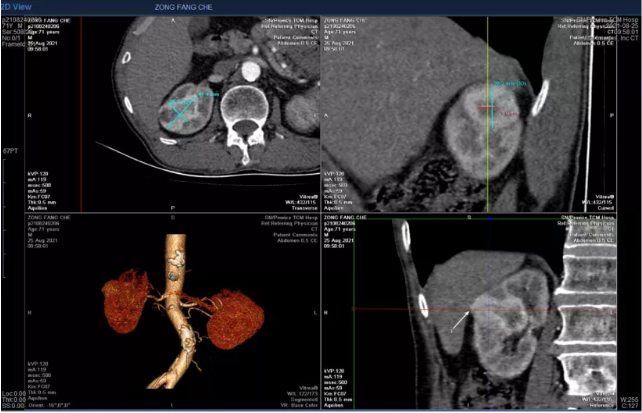

患者为一71岁男性,入院四个月前体检时发现右侧肾脏一占位性病变。入院后进一步行泌尿系增强CT提示恶性肿瘤可能性极大,如下图所示,肿瘤位于右肾中上部,与肝脏毗邻,右肾动脉前支前上段及前下段包绕肿瘤,而且右肾存在副肾,手术难度以及手术风险也随之增加,一旦肾脏动脉破裂出血,肾脏全切术不可避免,将严重影响生活质量。